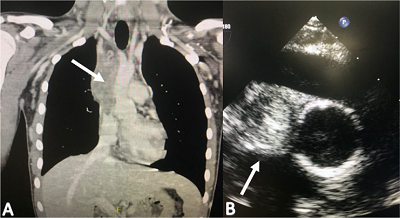

The patient underwent bilateral internal jugular vein to SVC bypass surgery with interposition of a reversed SFV autograft harvested from the left lower limb. Through a medium sternotomy extending to the neck, the thrombosed SVC and brachiocephalic veins were identified, the graft was placed with an end-to-side proximal anastomosis to the SVC and an end-to-side distal anastomosis to the right and left internal jugular veins with an end-to-side neo-confluent, this was performed without using cardiopulmonary bypass (Figure 2). The patient was taken to the surgical intensive care unit, extubated after six hours, and transferred to a general ward on postoperative day one. He was discharged after five days on full oral anticoagulation and a comprehensive rehabilitation plan.

Follow-up was conducted with venous phase computed tomography angiography (CTA) (Figure 3). The patient continued management with full oral anticoagulation and lymphatic drainage to reduce pectoral and left upper limb edema. After a three-year follow-up, the patient is asymptomatic, fully resolved the SVCS, and has not required any additional interventions.